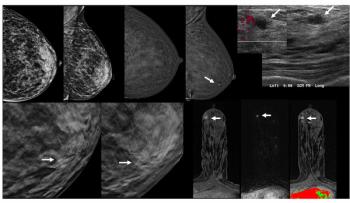

While the addition of contrast-enhanced mammography (CEM) to digital breast tomosynthesis (DBT) led to over a 13 percent increase in false positive cases, researchers also noted over double the cancer yield per 1,000 women in comparison to DBT alone.